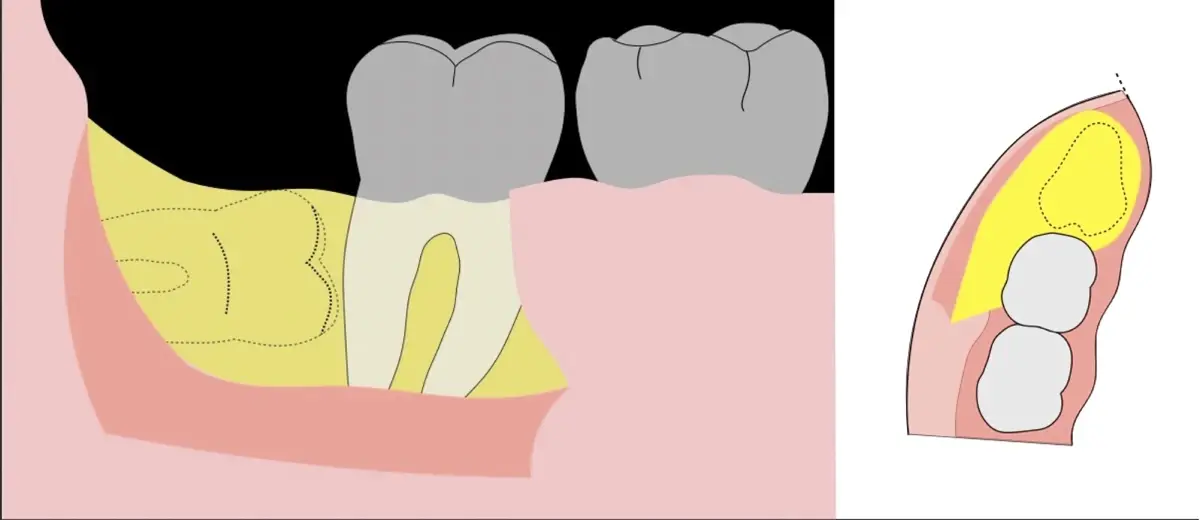

El procedimiento se inicia colocando anestesia troncular para bloqueo del nervio dentario inferior y sus ramas. Luego, se establecerá el diseño de acceso según la disposición de la molar a extraer. Para fines didácticos, se explicará cómo se realizaría la extracción de la molar de la Figura 1: se realiza una incisión horizontal a nivel de la zona retromolar hasta llegar a distal de la segunda molar, continuándose con una incisión intrasurcular hasta mesial de la segunda molar, finalizando con una incisión vertical a espesor total hasta llegar a la línea mucogingival (Figura 2).